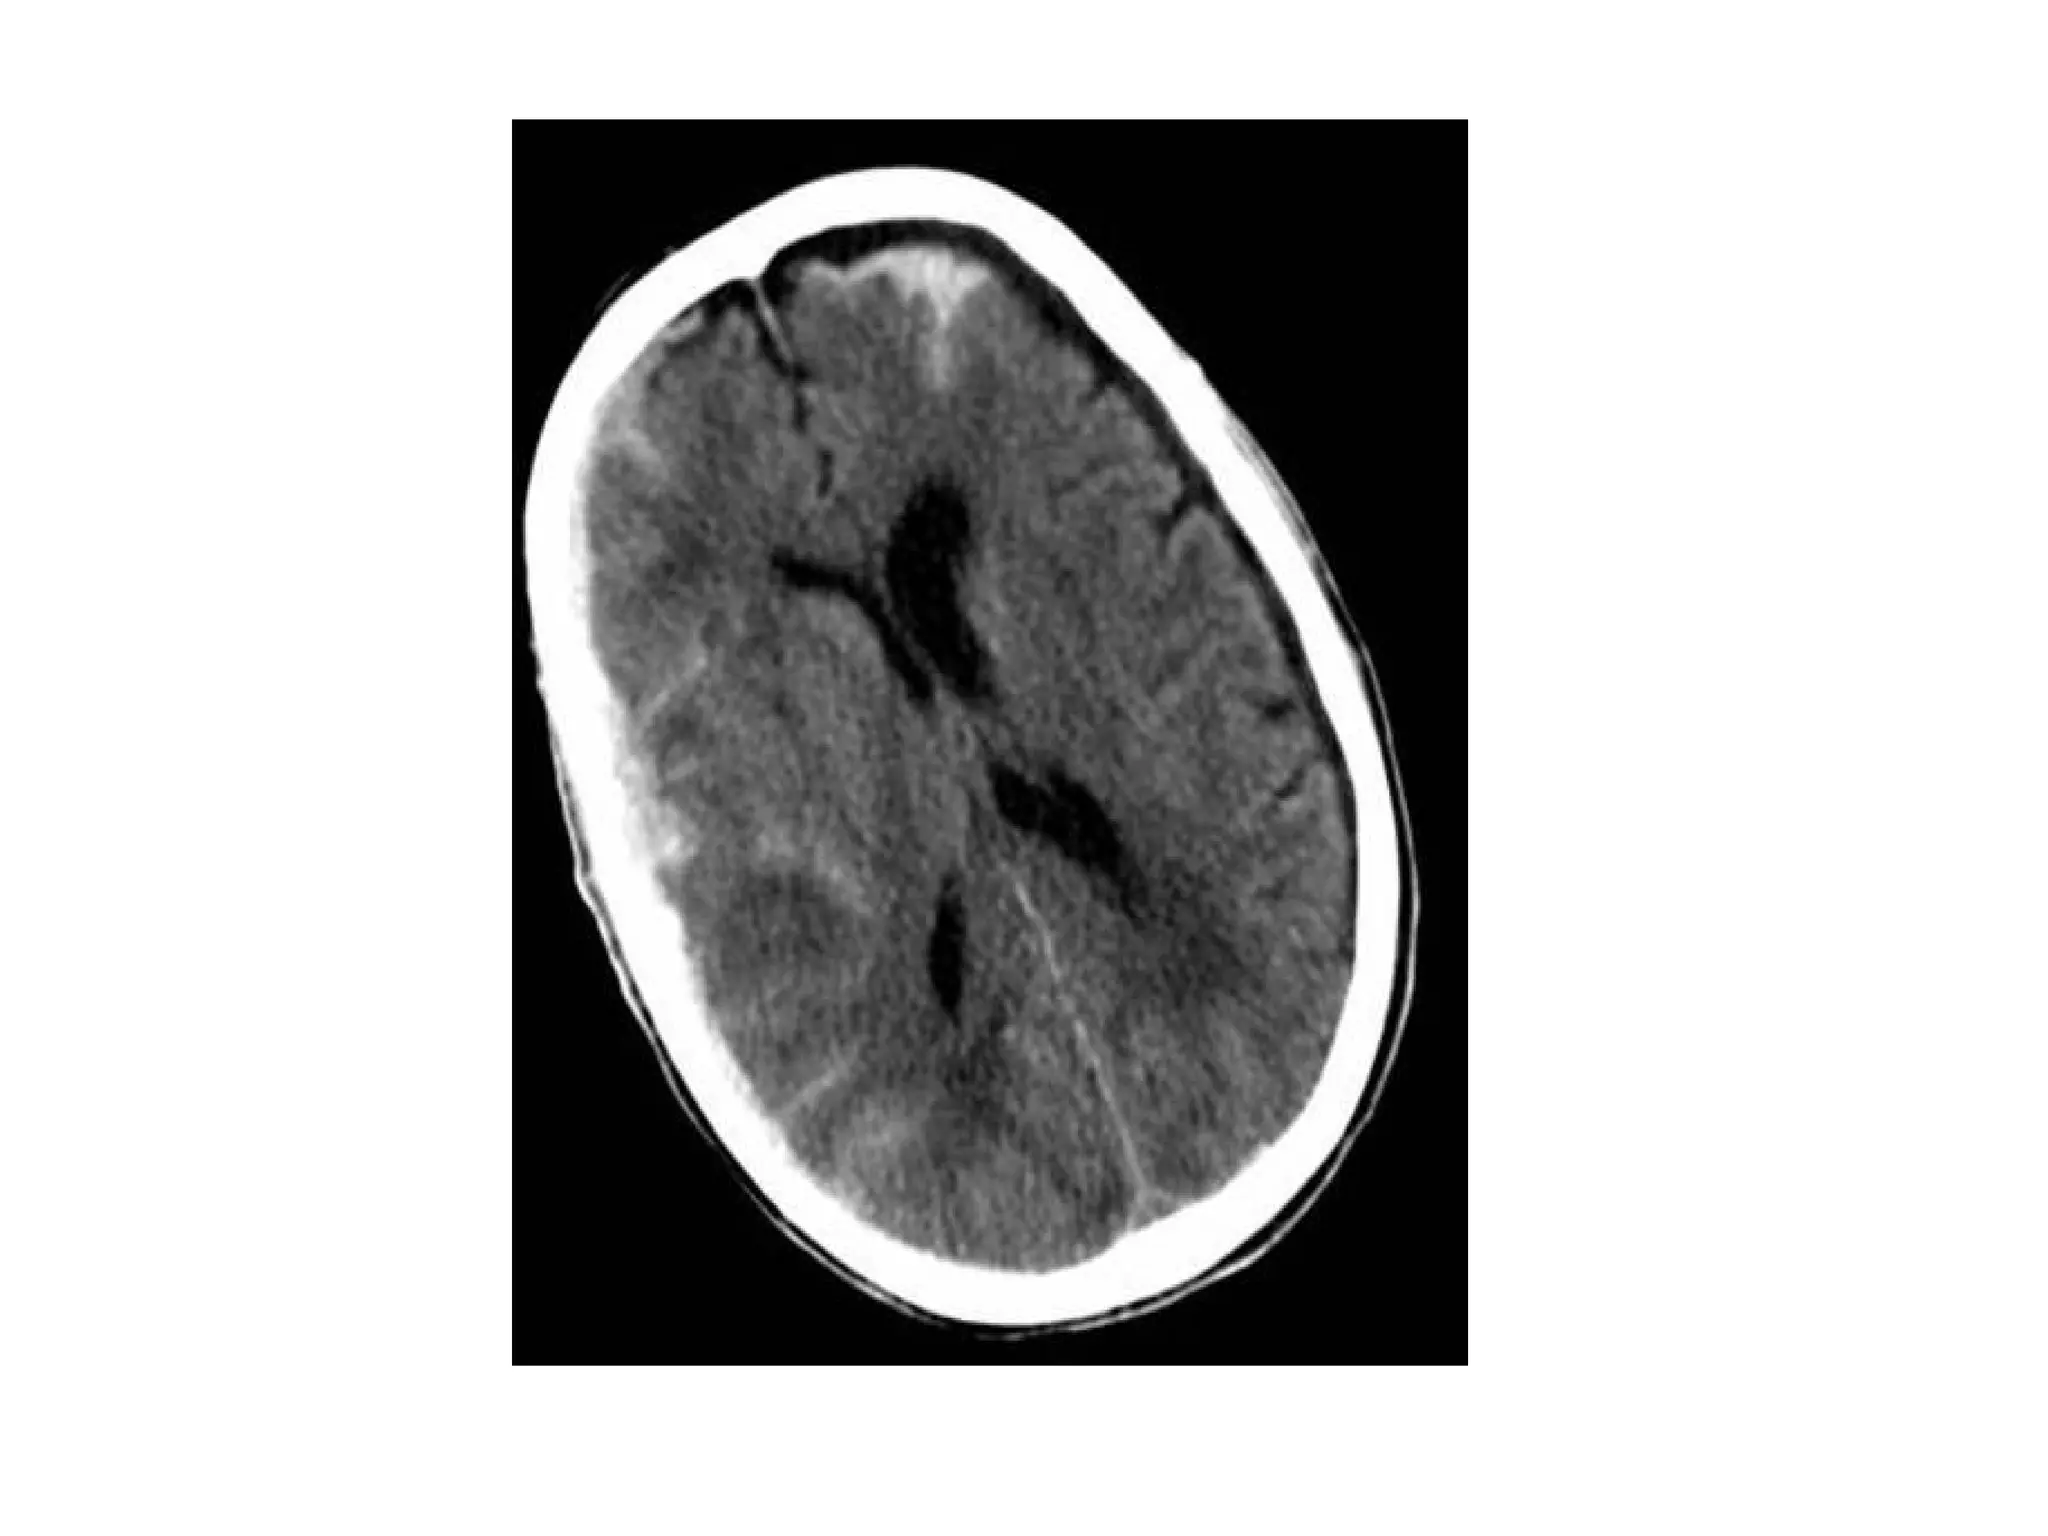

Thrombosis of deep cerebral veins

-The clinical presentation of thrombosis of the

deep cerebral venous system are severe

dysfunction of the diencephalon reflected by

coma and disturbances of eye movements and

pupillary reflexes , usually this results in a

poor outcome

-However , partial syndromes without a decrease in

the level of consciousness or brainstem signs

exist which may lead to initial misdiagnoses

-Deep cerebral venous system thrombosis is an

underdiagnosed condition when symptoms are

mild and should be suspected if the patient is a

young woman , if the lesions are within the basal

ganglia or thalamus and especially if they are

bilateral

Patient with deep cerebral vein thrombosis , notice the bilateral infarctions in

the basal ganglia

The same patient , there is absence of flow void in the internal

cerebral veins, straight sinus and right transverse sinus (blue

arrows) , on the MRA the right transverse sinus is not visualized